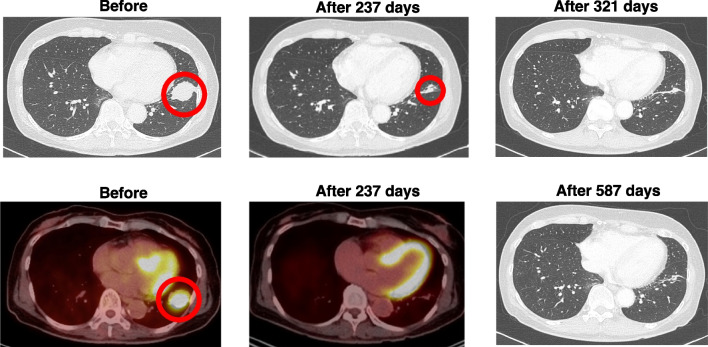

在中国,非小细胞肺癌(NSCLC)是发病率和死亡率最高的恶性肿瘤。其中,约40%-50%的肺腺癌患者携带表皮生长因子受体(EGFR)基因突变。

近日,《Neuro-Oncology》在线全文发表了埃克替尼联合阿美替尼一线治疗EGFR突变伴脑转移非小细胞肺癌患者的疗效与安全性的一项I/II期临床研究的研究结果。